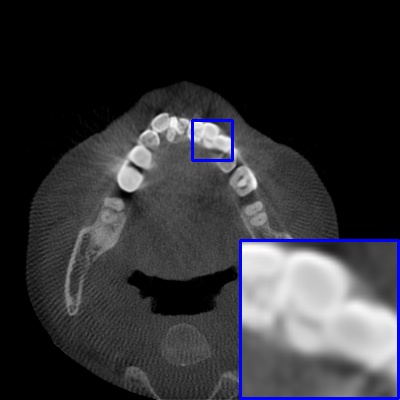

As a useful technology for radiographic imaging, Cone Beam Computed Tomography (CBCT) is widely utilized in oral surgery [1], orthodontics [2], and dental implant [3], etc. High-quality dental CBCT imaging is of great importance to guarantee accurate clinical diagnosis. However, the metal teeth implants would bring unpleasant metal artifacts like flare during the imaging process due to the radiation scattering and beam hardening effects [4]. These artifacts will somewhat damage the post-processing diagnosis-related tasks like tooth segmentation. For example, in Fig. 1, we present two CBCT images with or without flare artifacts contaminated by metals in teeth. The two images are segmented by a segmentation network [5] trained on large scale tooth CBCT images with accurate masks annotated by experienced dentists. One can see that, the CBCT image with metal artifacts are inaccurately segmented with heavy missing of teeth area, which cannot be used to infer the teeth structure. To this end, it is essential to remove the metal artifacts on the dental CBCT images with metal implants for the following usage of tooth segmentation in clinical diagnosis.

Refer to caption (a) MA-free Image

Refer to caption (b) Segmentation on (a)

Refer to caption (c) MA Image

Refer to caption (d) Segmentation on (c)

Figure 1: Segmentation results by Poolformer [5]. (a) A CBCT image without metal artifacts. (b) Segmentation mask of Poolformer on (a). (c) The image (a) with synthetic metal artifacts. (d) Segmentation mask of Poolformer on (c).